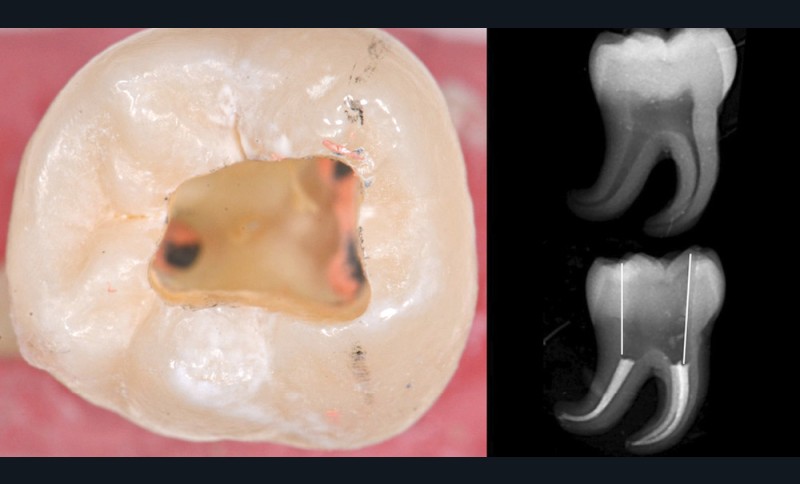

Une cavité d’accès moderne, dictée par l’anatomie et la pathologie de la dent, optimiserait à la fois les pronostics endodontiques et biomécaniques et donc la longévité de la dent sur l’arcade (patient-centered dentistry ou dentisterie centrée sur le patient) (fig. 5).